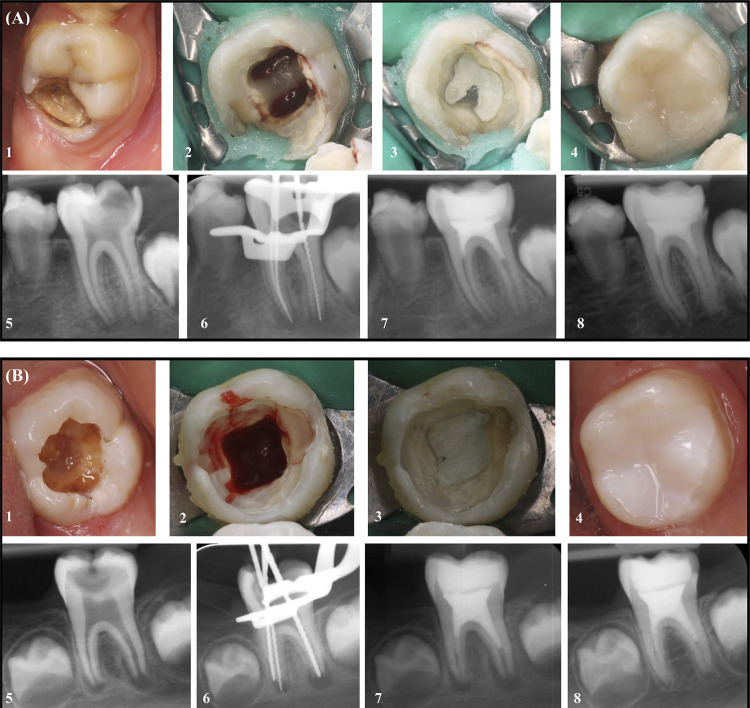

Objective: The primary goal is to evaluate the effects of two different intracanal medicaments, calcium hydroxide [Ca(OH)2] and double antibiotic paste (DAP), on radiographic outcomes during regenerative endodontic procedures (REP) of immature permanent mandibular first molars with symptomatic irreversible pulpitis and symptomatic apical periodontitis (SIP/SAP). Additionally, the secondary goal was to evaluate MMP-8 levels during REP using two different intracanal medicaments.

Methodology: The study included 20 patients with immature mandibular first molars exhibiting SIP/SAP. Participants were randomly assigned into two groups based on the applied intracanal medicament. Ca(OH)2 (n=10) was prepared by mixing it with sterile distilled water, while the same amount of powdered metronidazole and ciprofloxacin were mixed and combined with sterile distilled water for DAP (n=10). MMP-8 in periapical samples were measured at baseline and on the 14th day using immunofluorometric assay. Image-J software with TurboReg plug-in was utilized to determine changes in root length, root width, radiographic root area (RRA) during the 12-month follow-up period. Data were analyzed by SPSS 25.0 (p<.05).

Results: Significant increase in MMP-8 on the 14th day compared to baseline in both groups (p<0.001). There was no significant difference between the two groups in terms of the increase in MMP-8 (p>0.05). Root length significantly increased in both groups (p=0.001), with Ca(OH)2 showing a greater increase (p=0.046). Root width and RRA increased similarly in both groups at 12th month.

Conclusion: Both Ca(OH)2 and DAP applications resulted in a significant increase in periapical MMP-8 levels. Increase in radiographic root width and root area was similar between two groups, but Ca(OH)2 led to a significantly greater increase in root length. Further studies with larger sample sizes are necessary to validate our findings during REP of vital immature permanent mandibular molars. Clinical Trials database: NCT05581706.